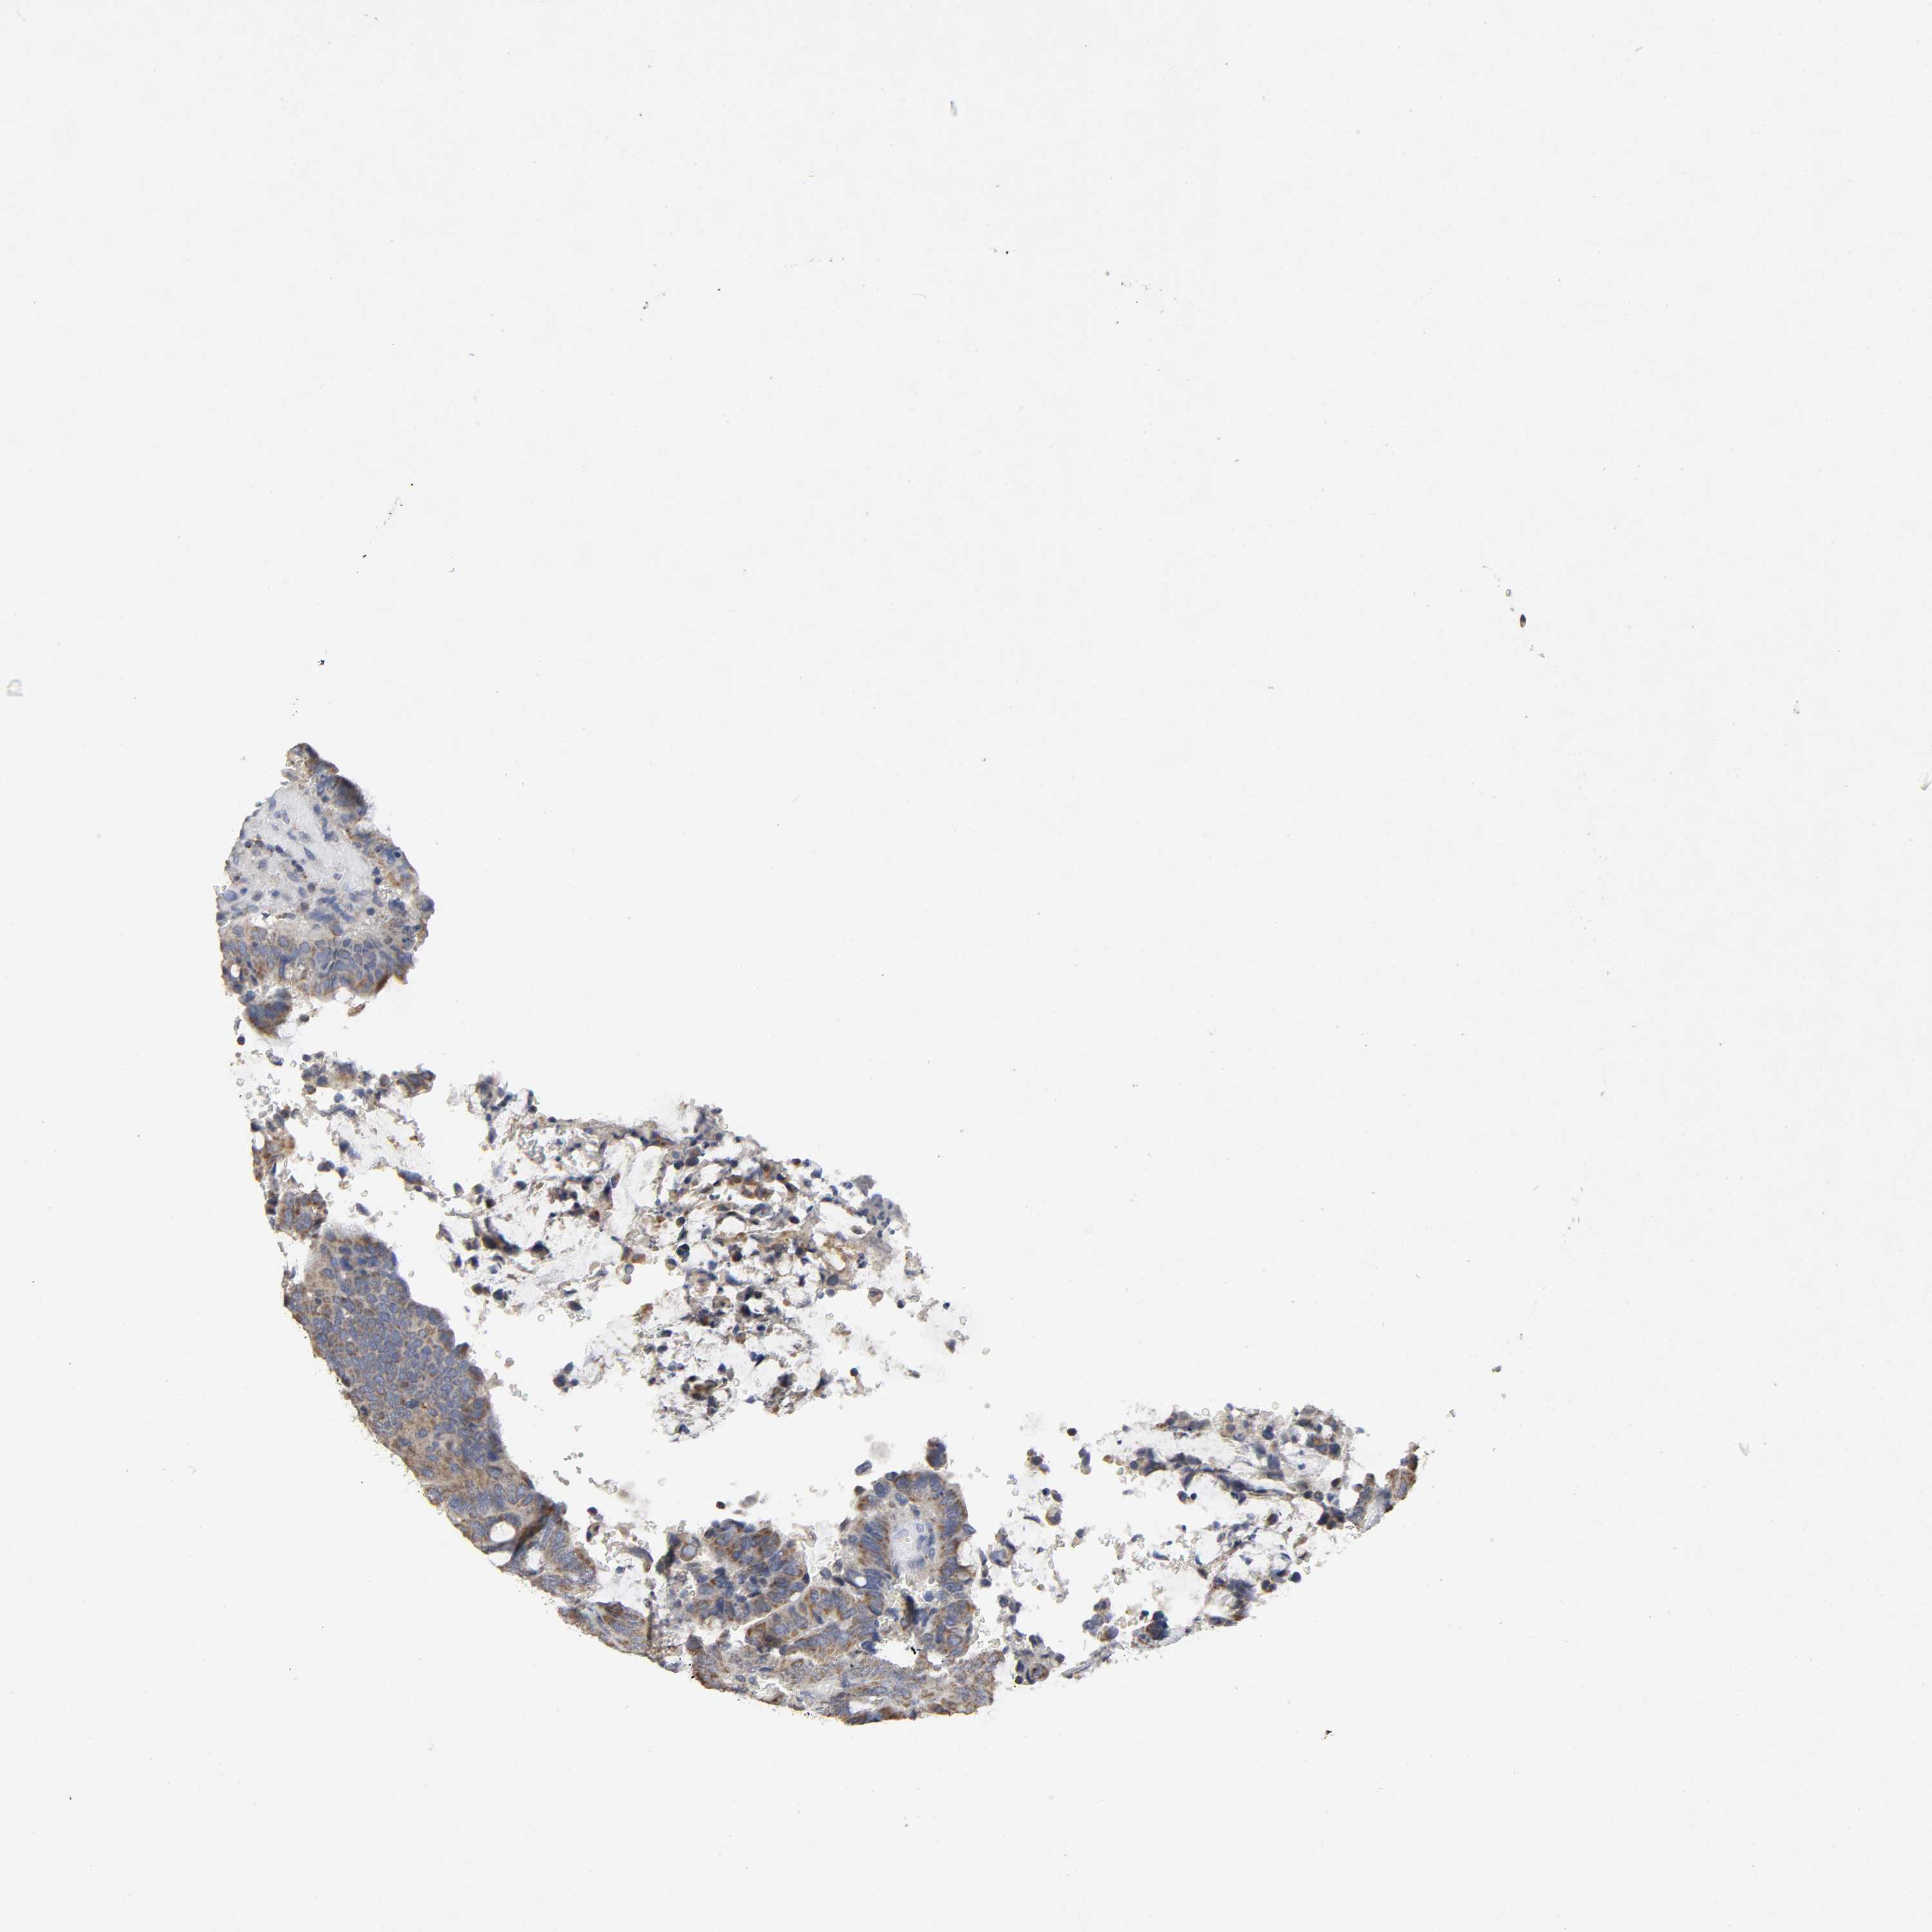

CANCER COLORECTAL CANCER Show tissue menu

Colorectal cancer

Human cancer

Colon adenocarcinoma